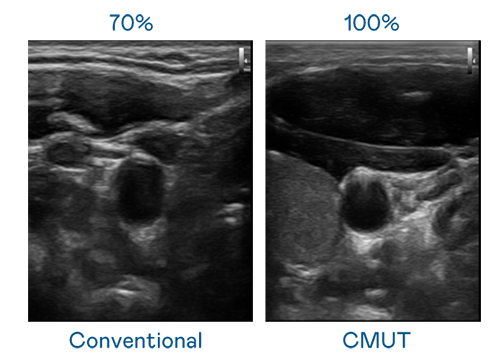

CMUT 技术是一种用电容式微机电元件来产生超音波讯号的技术。与传统 PZT 压电式技术相比,CMUT 频宽增加 30%,更宽频的超音波讯号让影像解析度大幅提升,是实现高影像品质医疗超音波扫描、促进精准医疗发展的关键技术。

超音波影像的解析度高低,首先取决于探头能发出的讯号频宽。腾博会 CMUT 可提供高清晰的超音波讯号,提供高频宽、高灵敏度、影像纹理细节更高的超音波影像,协助医护人员缩短影像判读时间及利用精准的医疗影像进行诊断。